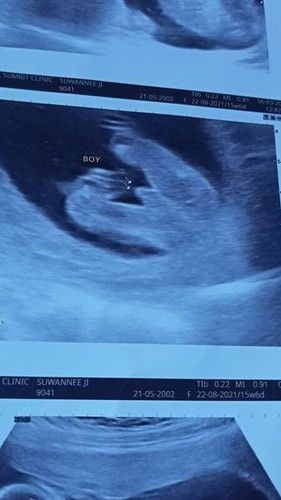

15w+6 สอบถามหน่อยค่า

หมอซาวด์แล้ว่าเป็น ผช.มีสิทออกมาเป็น ผญ.ไหมคะ ภาพมันชัดมากค่า #ขอบคุณล่วงหน้านะคะ #ท้องแรกคะ #ทีมสิงหา64

ได้ค่ะ !! โตขึ้นเดี๋ยวลูกก็เลือกเพจเองค่ะ...หยอกๆๆๆๆ อย่าไปเครียด 😁😁😁 คงต้องดู ความแม่นยำของเครื่องมือการตรวจค่ะ บางทีแค่รูปซาวด์ อาจไม่พอก็เป็นได้ รอดูต่อไปค่ะ #ทีมสิงหา64 เหมือนกัน #15w

คงไม่มีสิทธิ์เปลี่ยนแล้วล่ะ. ชัดขนาดนั้น

ชัดขนาดนี้หมดสิทธิ์แล้วค่ะคุณแม่